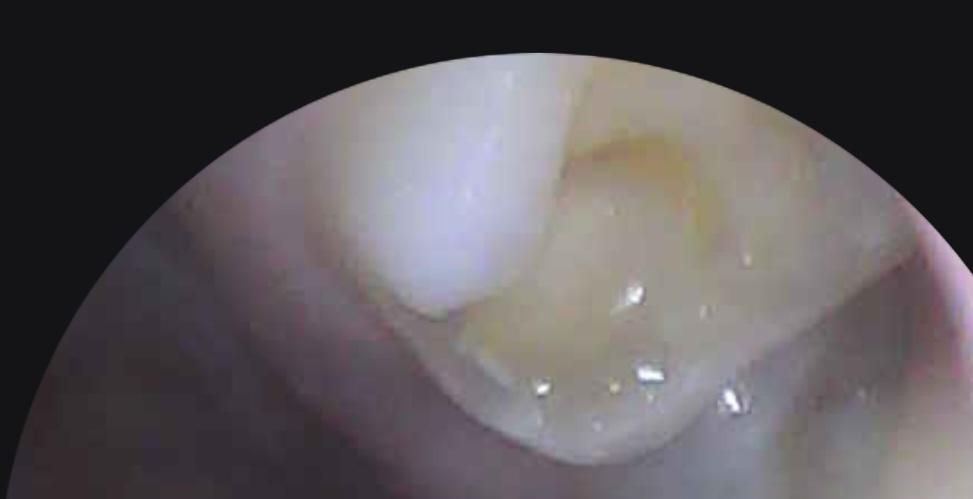

저번에 충치 레진치료했던 어금니가 깨졌어요.

19살 학생인데 예전에 충치 치료한지는 좀 됐구요. 오늘 껌 먹다가 치료한 어금니 옆면이 조금 많이 깨져서 내일 치과 가려고 하는데 이정도면 신경치료 안하고 인레이나 크라운 씌우려나요? 사진으로 봤을 때 충치는 없어 보이는데.. 통증도 정말 약하게 시린정도? 정말 신경치료안하고 싶어요 ㅠㅠ

• 1번 째 사진

치아를 너무 가깝게 촬영하여 잘 구분이 안갑니다. 다만 충치는 없어보이고 단순히 떨어져나간 것으로 보여 신경치료는 하지 않을 것 같습니다.